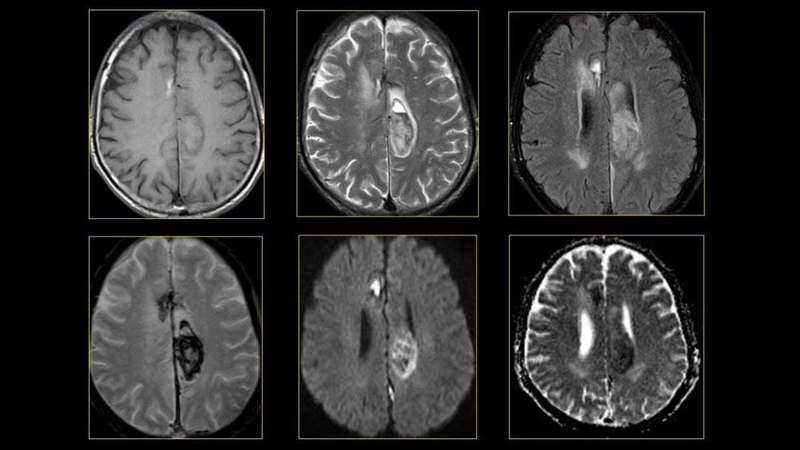

Trong chẩn đoán các bệnh lý về thần kinh, chụp cộng hưởng từ (MRI) giúp bác sĩ phát hiện được tình trạng sức khoẻ của người bệnh như phình mạch máu não, các chấn thương ở não do tai nạn, rối loạn tủy sống, khối u não

Chụp MRI là gì? Những điều cần biết về kỹ thuật chụp MRI 2 Chụp MRI sọ não trong chẩn đoán bệnh lý về thần kinh

Nhờ có kỹ thuật chụp cộng hưởng từ (MRI) mà hình ảnh giải phẫu của não và các mạch máu xung quanh trở nên rõ ràng giúp xác định chính vùng bị tổn chấn thương. Từ đó, bác sĩ có thể căn cứ đưa ra phác đồ điều trị phù hợp.